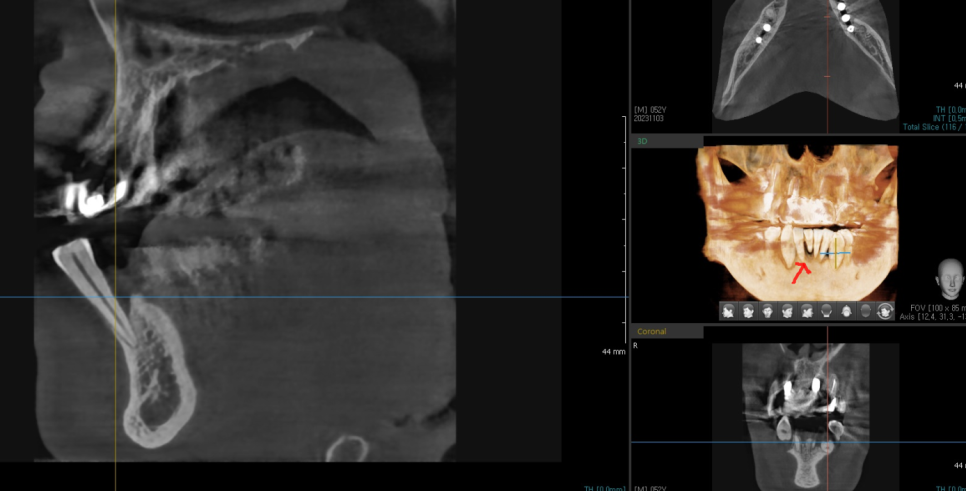

파노라마만 찍어도 확인이 가능하고

ct는 더 정확합니다.

패인것까지 보이거든요.

231103

실제로 잇몸을 열어보았을 때

ct에서 보이는대로 구멍이 나고 파여 있습니다.

이 상태에서 임플란트는 심을 수 있지만

추후에 어떻게 될까요?